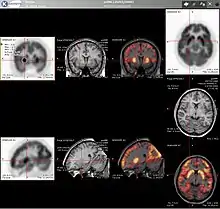

Combination of PET with CT or MRI

PET scans are increasingly read alongside CT or MRI scans, with the combination (co-registration) giving both anatomic and metabolic information (i.e., what the structure is, and what it is doing biochemically). Because PET imaging is most useful in combination with anatomical imaging, such as CT, modern PET scanners are now available with integrated high-end multi-detector-row CT scanners (PET-CT). Because the two scans can be performed in immediate sequence during the same session, with the patient not changing position between the two types of scans, the two sets of images are more precisely registered, so that areas of abnormality on the PET imaging can be more perfectly correlated with anatomy on the CT images. This is very useful in showing detailed views of moving organs or structures with higher anatomical variation, which is more common outside the brain.